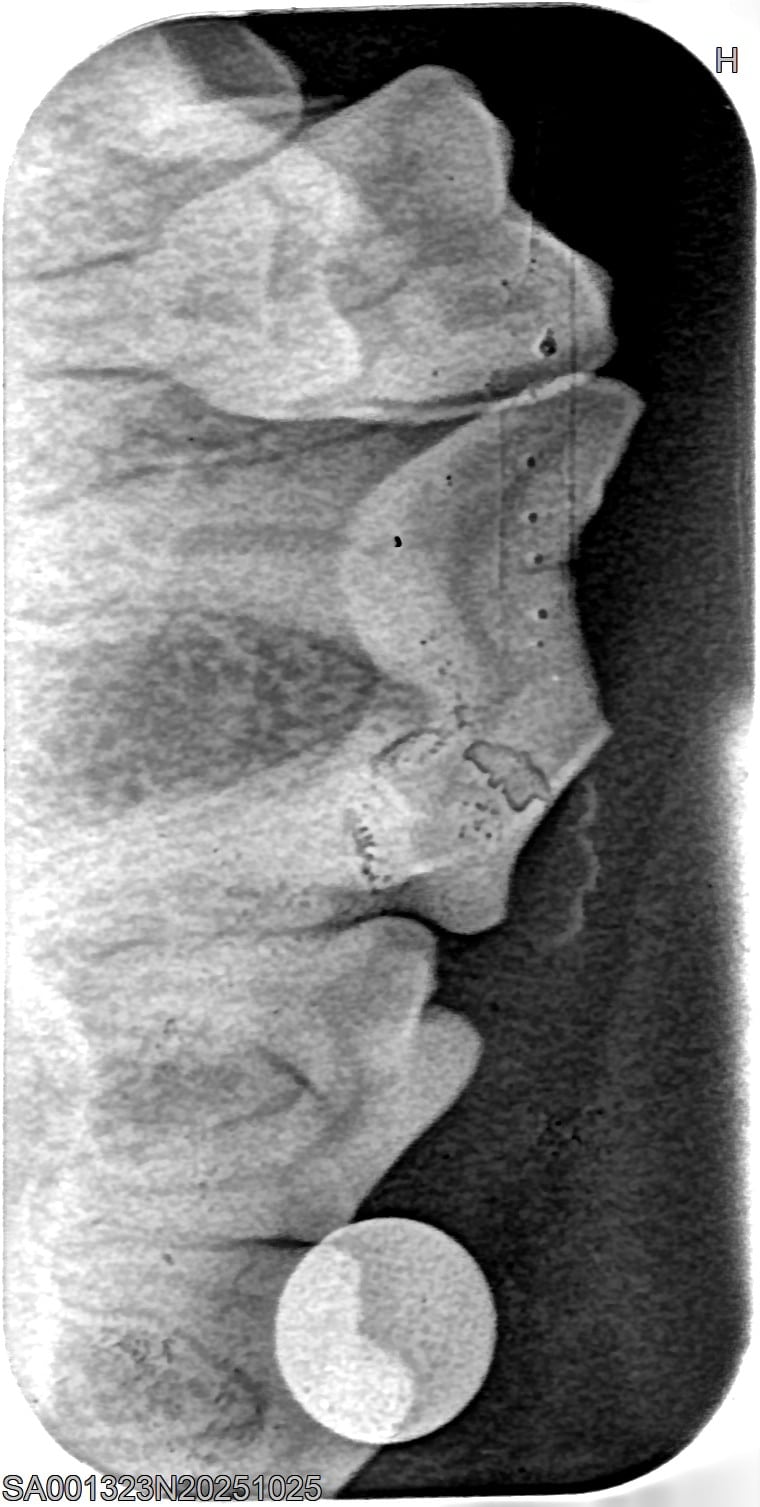

Um das Ausmaß von Zahnstein und möglichen Folgeschäden richtig zu beurteilen, ist eine tierzahnärztliche Untersuchung erforderlich. Neben der Sichtkontrolle werden häufig Röntgenaufnahmen der Zähne angefertigt, um Entzündungen oder Veränderungen unter dem Zahnfleisch zu erkennen. So kann der Tierarzt gezielt entscheiden, welche Zähne erhalten werden können und wo eine Behandlung notwendig ist. Eine frühzeitige Diagnostik hilft, Schmerzen zu vermeiden und die Zahngesundheit des Hundes langfristig zu sichern.

Behandlung von Zahnstein beim Hund

Röntgenbilder

(Fraktur + Wurzelentzündung durch Zahnstein)